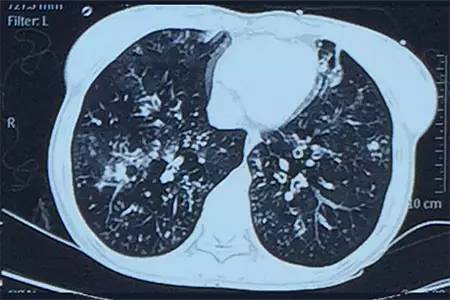

肺CT見下圖

該患者肺部影像學(xué)表現(xiàn)為明顯的支氣管擴(kuò)張,同時(shí)伴有彌漫的滲出斑片影,考慮合并感染,細(xì)菌學(xué)培養(yǎng)提示為綠膿桿菌,結(jié)合藥敏結(jié)果給予頭孢他啶+阿米卡星抗感染,患者存在II型呼吸衰竭予氣管插管機(jī)械通氣支持,加強(qiáng)體位引流排痰,治療18天,患者情況好轉(zhuǎn)出院。